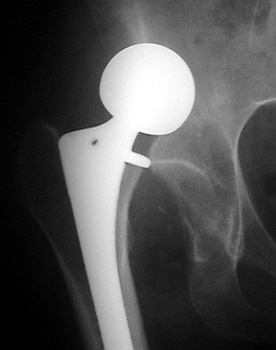

Dislocated femoral component secondary to loose acetabular cup

with reverse acetabular inclination